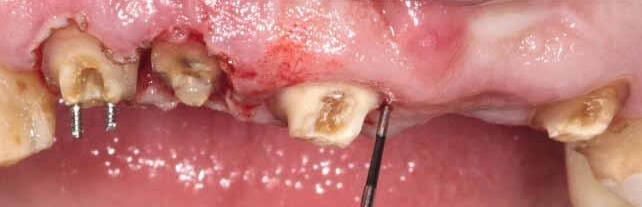

Fig 5. Central incisors extracted using minimally invasive protocol. Alveolar bone and gingival tissues were intact after extraction

Fig 6. BioHorizons Tapered Pro Conical implants of 3.8 x 15mm placed according to the plan.

Fig 7. Implants immediately after installation.

Fig 8. Scanbody installation for custom abutment and definite restoration fabrication.

Fig 9. Periapical radiograph for verification of proper seating of the scanbodies.